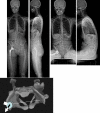

Introduction: The role of the pelvic area in sagittal balance is evident for spinal surgeons, but the influence of the coxofemoral joint is underestimated and inadequately explained by conventional imagery. Comprehensive analysis of the pelvic and subpelvic sectors as part of the sagittal, frontal and cross-sectional balance of the trunk sheds new light on some spinal diseases and their relation to the pelvis.

Methods: This analysis, based on innovative radiologic methods as the EOS(®) technology but also on a new look at conventional imaging makes it possible to better analyze standing lateral images and seated images.

Results: Disturbances can come from atypical morphotypes or from unusual postures as in aging spine. The measurement of available extension and the concept of available flexion provide new information regarding individual's adaptation to the imbalance induced by disorders of the spine or lower limbs.